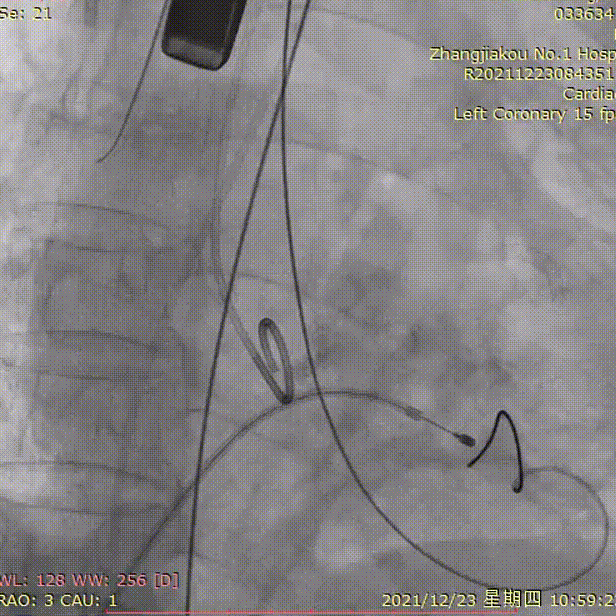

手术过程

LCA术前

LCA术后

根部造影

20mm球囊预扩

输送器过弓